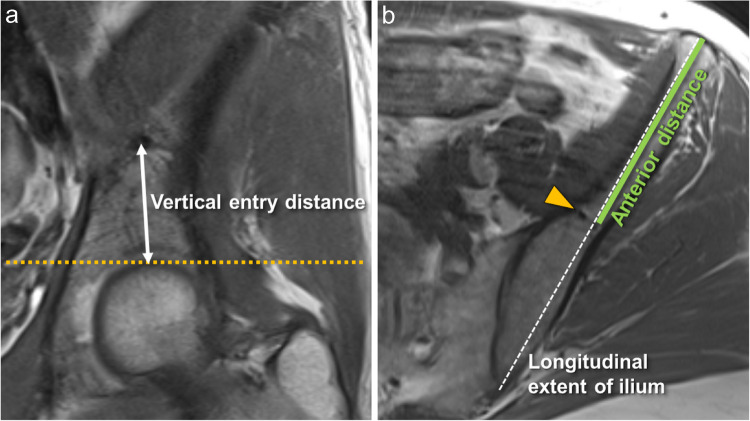

Materials and methods: MRI-examinations of the pelvis in 245 patients were analyzed retrospectively. Prominent nutrient vessels of the ilium were recorded, including vessel origin, anatomical characteristics such as branches, bone-marrow changes, and entry points into the bone.

Results: Two hundred forty-five patients (54±16 years, range 18-88, 102 males) were included. Prominent central nutrient vessels were found in virtually all patients on both sides of the ilium. All nutrient vessels arose from the iliolumbar artery, forming a breakthrough-anastomosis to the superior gluteal artery. Two branches were seen in 57.6% on the right and 61.2% on the left side, constituting the most prevalent branching pattern. Three branches were seen in a third for each side. One or four branches were seen in 3-4.5% for both sides. A prominent branching pattern we coined "central-vessel-convolute" (CVC) at the central part of the ilium was seen in 75% on either side. Perivascular fatty areas were found in 25% of cases, and in 3.7-2.4% adjacent bone-marrow edema was observed.

Conclusion: Prominent nutrient vessels in the ilium are seen in almost all individuals, the majority exhibiting a specific CVC-pattern. These vessels may be surrounded by perivascular fatty areas; adjacent bone-marrow edema is rare. Recognizing the CVCs and the associated imaging findings should facilitate distinguishing normal anatomical structures from pathology.